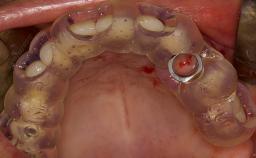

- Details of surgical techniques for SFE